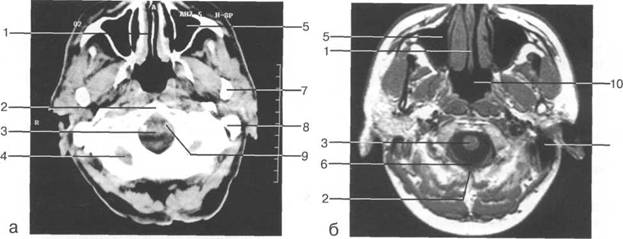

Задняя череп 13513u2010n 85;ая ямка представляет собой часть основания череп 13513u2010n 72;, ограниченную централь

Следует отметить, что в настоящее время оптимальным методом исследования структур задней череп 13513u2010n 85;ой ямки является МРТ, которая, в отличие от КТ, лишена артефактов от кост

Мозжечок заполняет практически весь объем задней череп 13513u2010n 85;ой ямки. Его поперечный раз

Следует остановиться на анатомии подпаутинных пространств задней череп 13513u2010n 85;ой ямки IV 20 мм. Между основанием череп 13513u2010n 72; и нижней поверхностью мозга от большого затылочного отверстия вдоль ската и спинки турецкого седла простирается задняя базальная цистерна. В зави IV